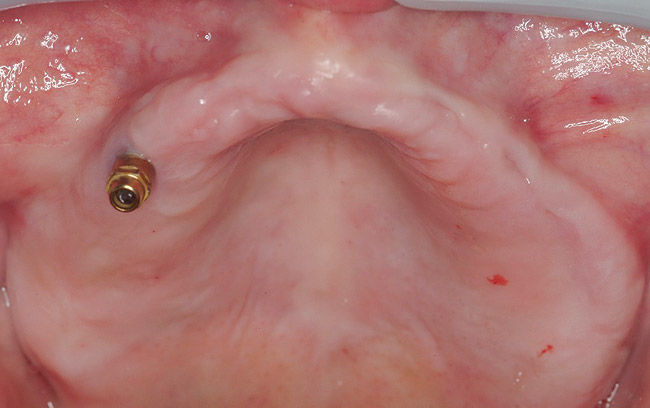

A 54-year-old woman who had been edentulous for more than 10 years presented to the author’s practice. She had previously undergone implant therapy in her mandibular left posterior sextant, and recently had a “mini”-implant procedure in the remainder of her mandibular arch, supporting a removable prosthesis. She also had several mini implants placed in her maxilla and an overdenture fabricated. Three of the four implants did not achieve osseointegration and were removed by her dentist. The mini implant in the maxillary right first bicuspid position served as a retentive anchor for a full denture (Figure 13 and Figure 14).

Figure 13  In Case 2, a mini implant in the maxillary right first bicuspid position served as a retentive anchor for a full denture.

Figure 13

Figure 14